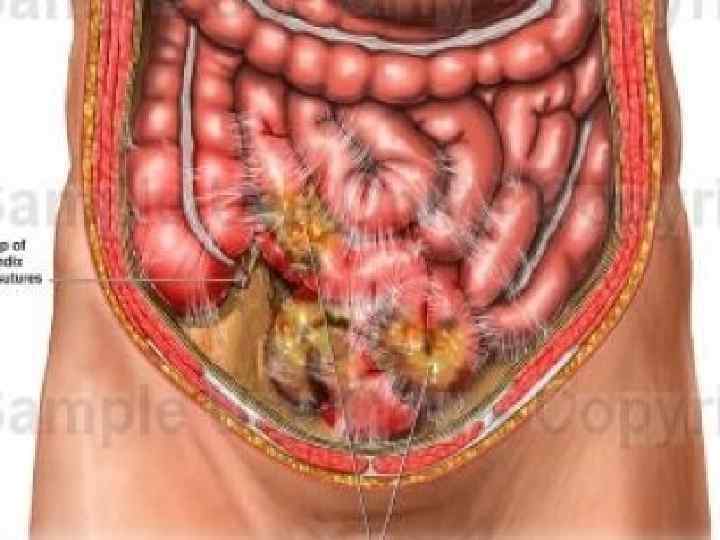

Перитонит – воспаление брюшины в результате интраабдоминального инфицирования. Первичный перитонит – развивается в результате гематогенного или лимфогенного инфицирования брюшной полости при отсутствии внутрибрюшного источника или транссудации специфической моноинфекции из других органов. Вторичный перитонит – наиболее частая и тяжелая форма абдоминальной инфекции, развивающейся в результате гнойно некротических заболеваний и повреждений полых и паренхиматозных органов живота и (или) осложнений в послеоперационном периоде (например, несостоятельность анастомоза). Третичный перитонит характеризуется персистирующим течением инфекционного процесса и развивается позже 48 ч. после успешного и адекватного хирургического лечения источника вторичного перитонита в результате контаминации брюшной полости полирезистентной нозокомиальной микробной флорой на фоне кишечной недостаточности

1. Основной диагноз; 2. Характер развития: Классификация 2. 1. Первичный; 2. 1. 1. Спонтанный перитонит у детей; 2. 1. 2. Спонтанный перитонит у взрослых; 2. 1. 3. Перитонит, связанный с определенными заболеваниями (туберкулез, сифилис, гонорея); 2. 2. Вторичный; 2. 3. Третичный; 3. Распространенность: 3. 1. Местный (занимающий одну две анатомические области); 3. 1. 1. Отграниченный (инфильтрации, абсцесс); 3. 1. 2. Не отграниченный; 3. 2. Распространенный; 3. 2. 1. Диффузный (от трех до пяти анатомических областей или в пределах одного этажа брюшной полости); 3. 2. 2. Разлитой (более пяти анатомических областей или два этажа брюшной полости) 4. Экссудат и его примеси: 4. 1. Характер экссудата: серозный, фибринозный, гнойный, геморрагический (и их сочетания) 4. 2. Примеси: кишечное содержимое, желчь, моча, кровь

Анамнез Клинические проявления распространённого перитонита многообразны и складываются в большинстве случаев из симптомов основного заболевания и «наслоения» на них признаков воспаления брюшины, абдоминального сепсиса или септического шока. Наиболее часто больные жалуются на боль в животе, которая может быть острой или тупой. Первоначально, боль может быть слабой не локализованной, но затем она прогрессирует и усиливается при любом движении (например, кашель, сгибание бедра) и локальной пальпации. При сборе анамнеза выясняется давность заболевания, изменение характера и локализации боли, динамику токсических проявлений, признаки осложнений. Анамнез так же включает в себя предыдущие эпизоды болезней (например, дивертикулит, язвенную болезнь желудка и 12 перстной кишки). Анорексия и тошнота – частые симптомы и могут предшествовать возникновению боли в животе. Тошнота и рвота в начале заболевания носят рефлекторный характер. Температура тела обычно субфебрильная, реже она достигает вы соких цифр. Имеет место значительная разница между подмышечной и ректальной температурой (с м Маделунга). Нарушения стула не очень характерны, но по мере прогрессирования перитонита и пареза кишечника может быть задержка стула и отхождение газов

Клиническая картина Боль – сначала локализированная, затем диффузная, острейшая, больные кричат от нестерпимой боли. вынужденная поза – «эмбриона» . повышение температуры рвота – постепенно нарастающая, многократная. сухой язык – признак обезвоживания. нарушение моторики ЖКТ – жидкий стул, затем отсутствие любой перистальтики – запор. «гробовая тишина» – при аускультации живота. местная или распространенная ригидность мышц передней стенки. симптом Воскресенского. симптом Менделя. симптом Щеткина Блюмберга. тахикардия до 120 140 уд. /мин ректальное исследование – болезненность и выпирание передней стенки прямой кишки.